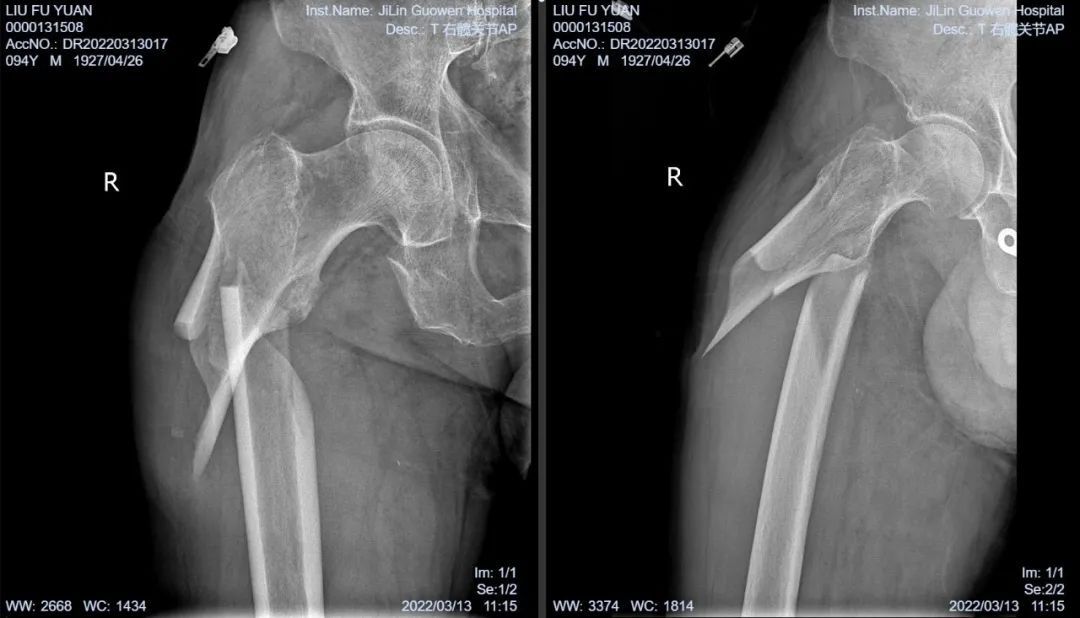

3月13日伴著急促的腳步聲、轆轆的車輪聲,夾雜著患者痛苦的呻吟聲,一位94歲的高齡老人被急診科醫(yī)護(hù)人員緊急送至骨科療區(qū)。這是怎么回事?呂國褔主任帶著值班醫(yī)生在做好防護(hù)措施后,第一時(shí)間來到患者病床前,經(jīng)急診科醫(yī)生診斷告知為 “股骨近端粉碎性骨折”,患者右大腿近端嚴(yán)重畸形,骨折端已經(jīng)刺穿前方肌肉直達(dá)皮下,局部皮膚高高隆起,局部皮膚有挫傷灶,呈青紫色,皮膚變薄,皮膚外可明顯觸及骨折斷端,右股骨X線片示:右股骨近端粉碎性骨折,斷端移位明顯,斷端銳利,近斷端位于前方皮膚下,局部皮膚隆起?;颊咛弁磩×?,痛苦難耐,測(cè)生命體征:血壓:220/110mmHg。